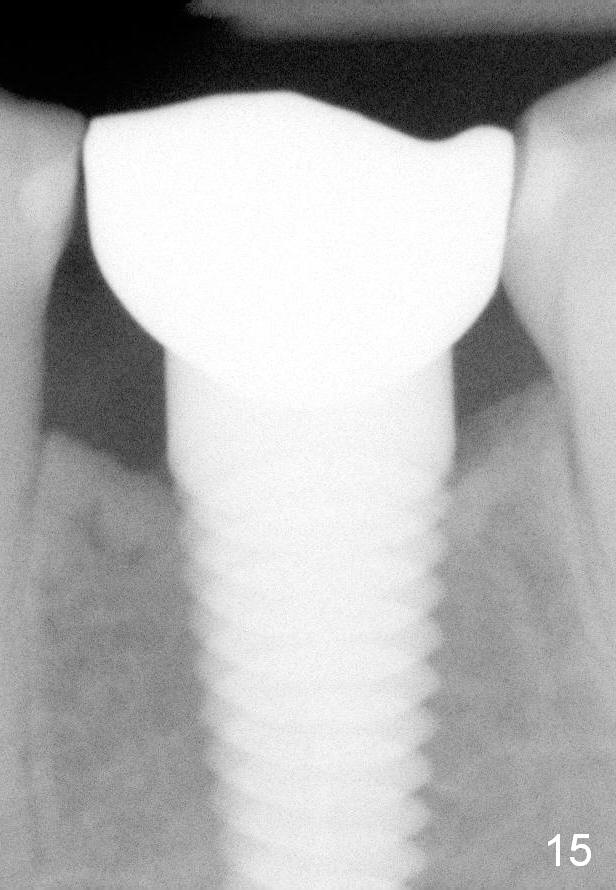

Eleven months post bonding (17 months postop), there is cortical bone formation at the mesial and distal crests (Fig.14). It remains the same 1 year 10 months post bonding (Fig.15). There is no bone loss 3 years 5 months post cementation (Fig.16). In fact the crestal cortical bone thickens.